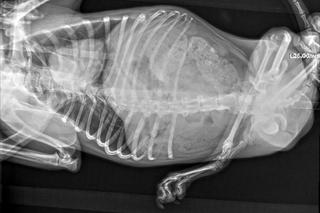

Szybko wyszło na jaw, że nie była jedynym psem na posesji, który potrzebował pomocy. W garażu (albo pomieszczeniu gospodarczym) pełnym brudu i śmieci żył jeszcze jeden piesek, którego stan zdrowia wprawił w osłupienie nawet fundację. Suczka, której później nadano imię Edi, ma bardzo zdeformowaną tylną część ciała, w tym tylne łapki.

- Deformacja psa obejmuje bardzo wiele kości i stawów. Najprawdopodobniej na skutek wypracowanego na swoje potrzeby sposobu poruszania się doszło także do zauważalnego skrzywienia kręgosłupa, który sam w sobie jest i tak znacząco skrócony. Edzia ewidentnie męczy się chodząc, a najgorsze jest to, że jej życie tak wygląda od co najmniej kilku lat - poinformowała Fundacja.